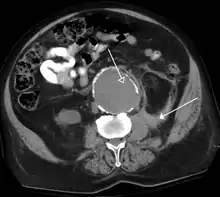

CT scan of a normal abdomen and pelvis | |